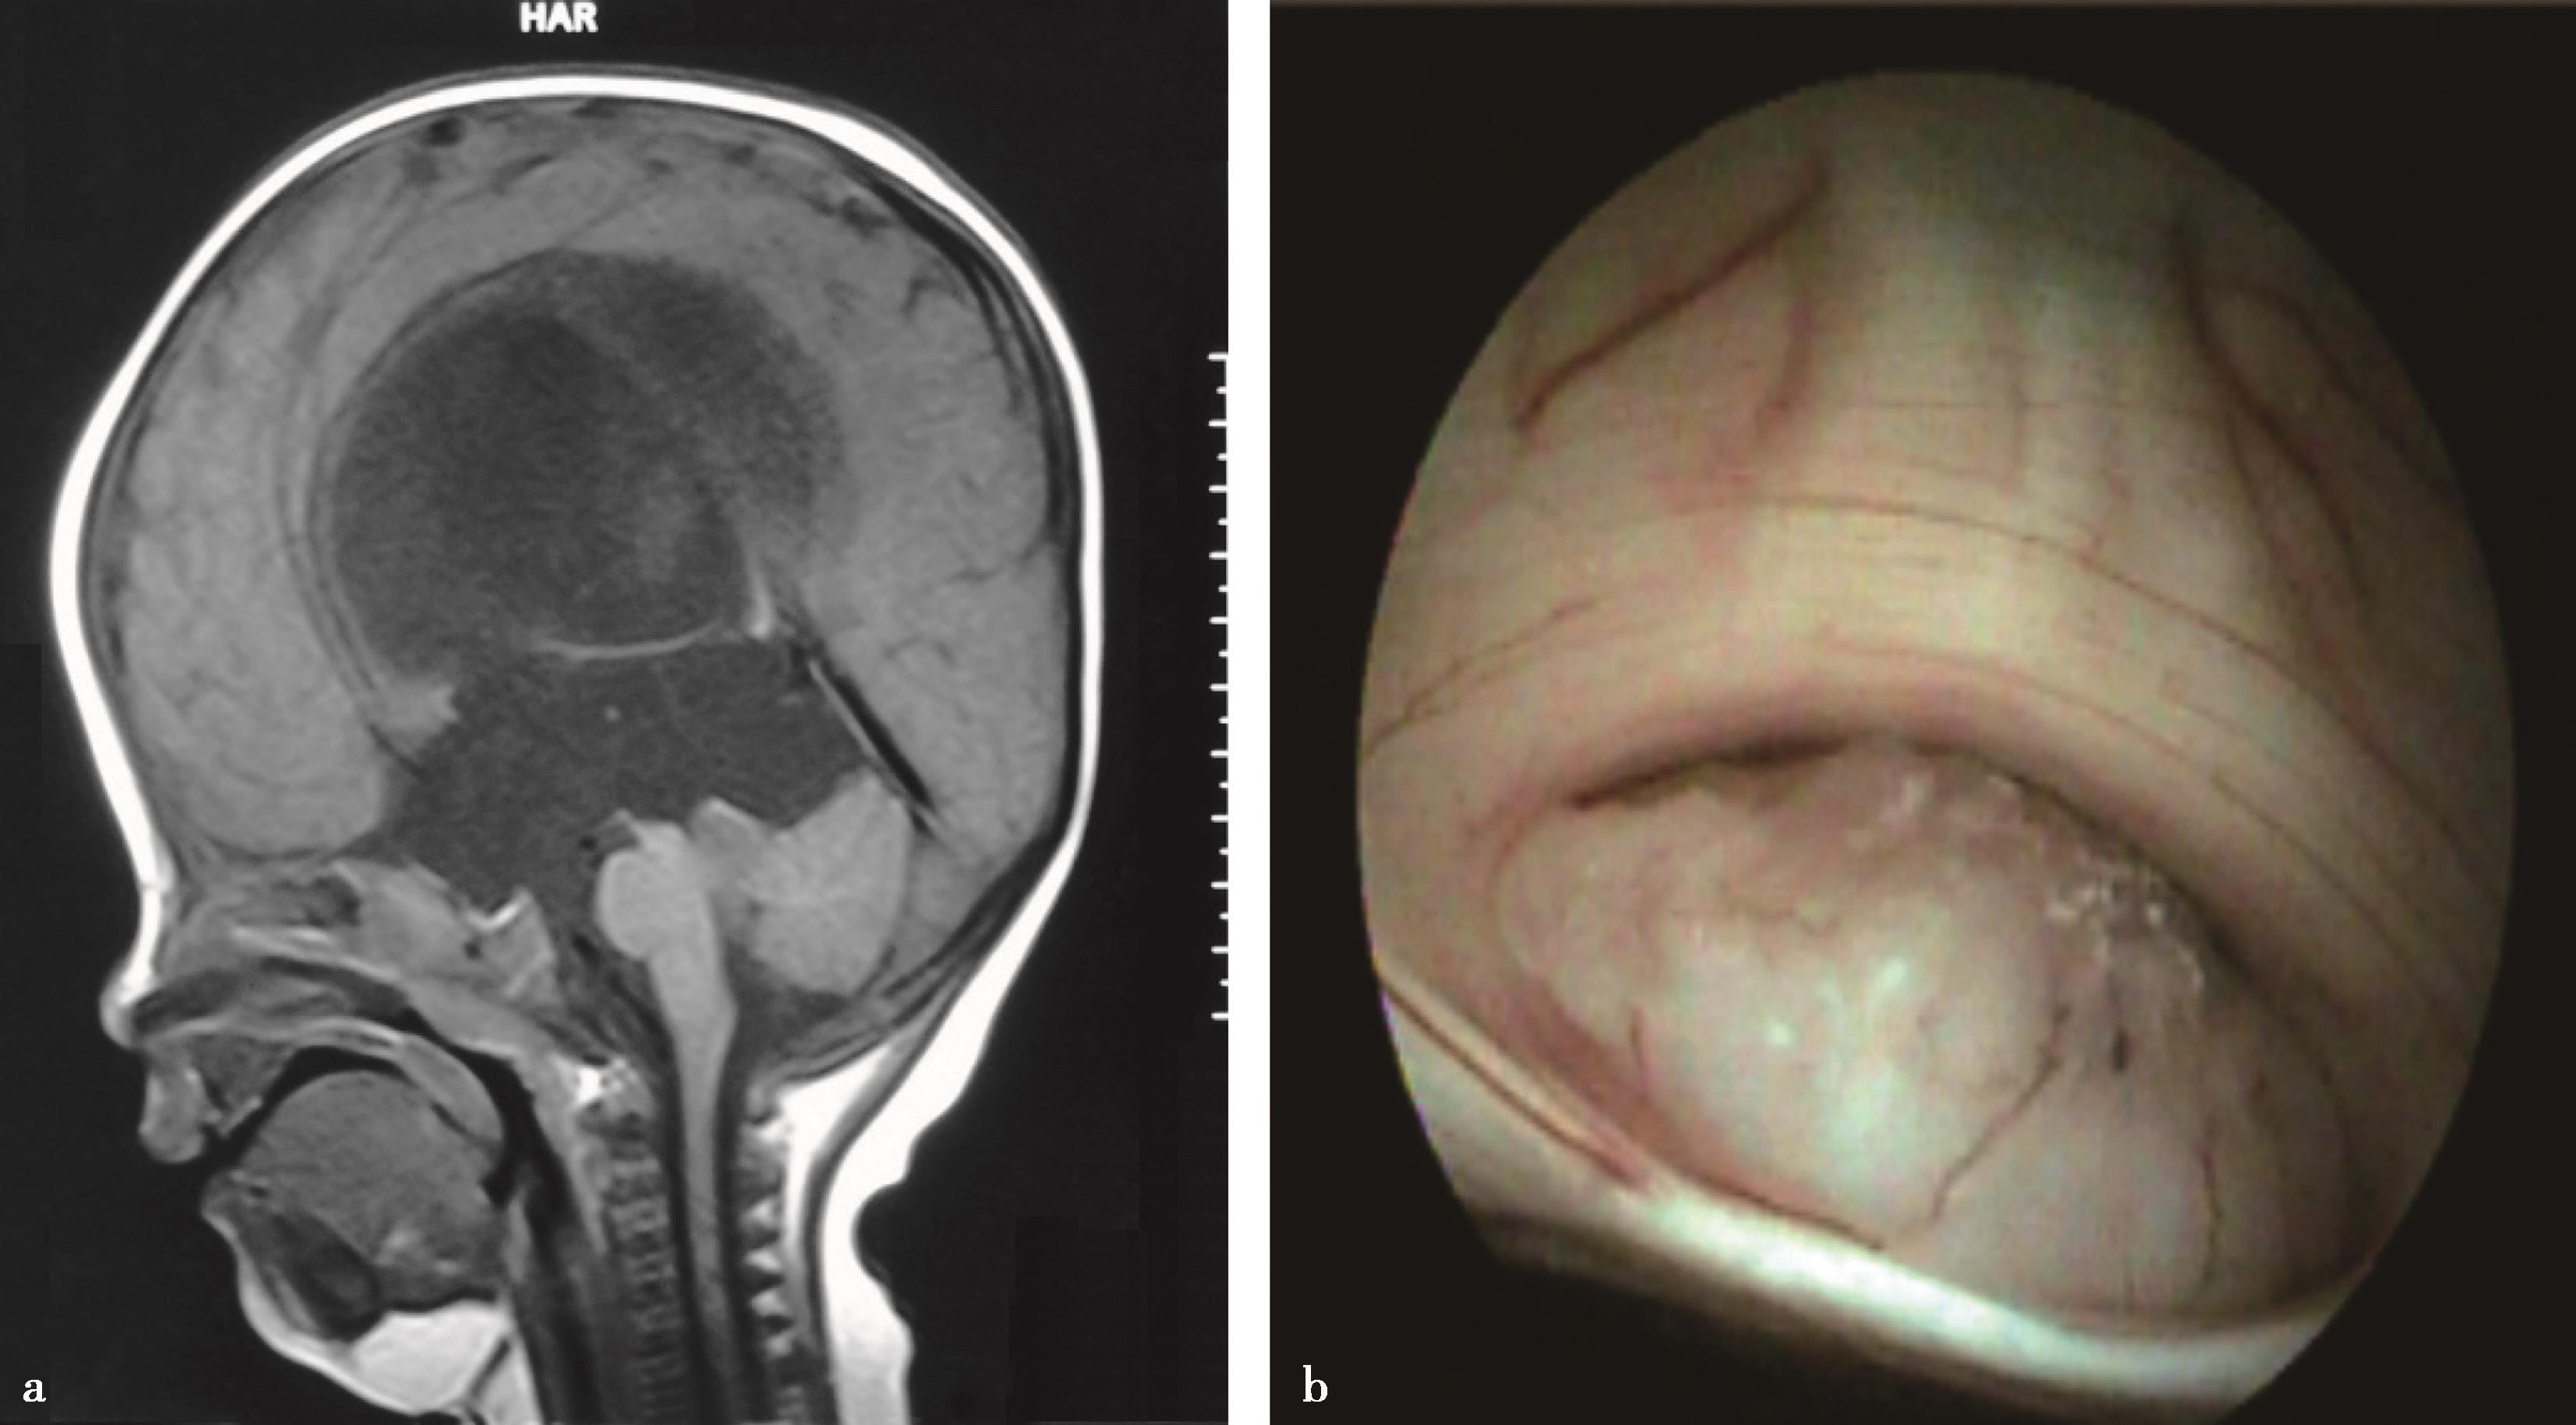

图3-1-1-1 出血后脑积水的脑室演变

a.发病时头颅CT:脑室内血肿呈高密度;b.发病12天后复查CT:血肿已呈低密度;c.发病5个月后头颅MRI:脑室明显扩张,脑室内未见异常信号;d.内镜下探查见脑室内仍有陈旧血斑及含铁血黄素沉积